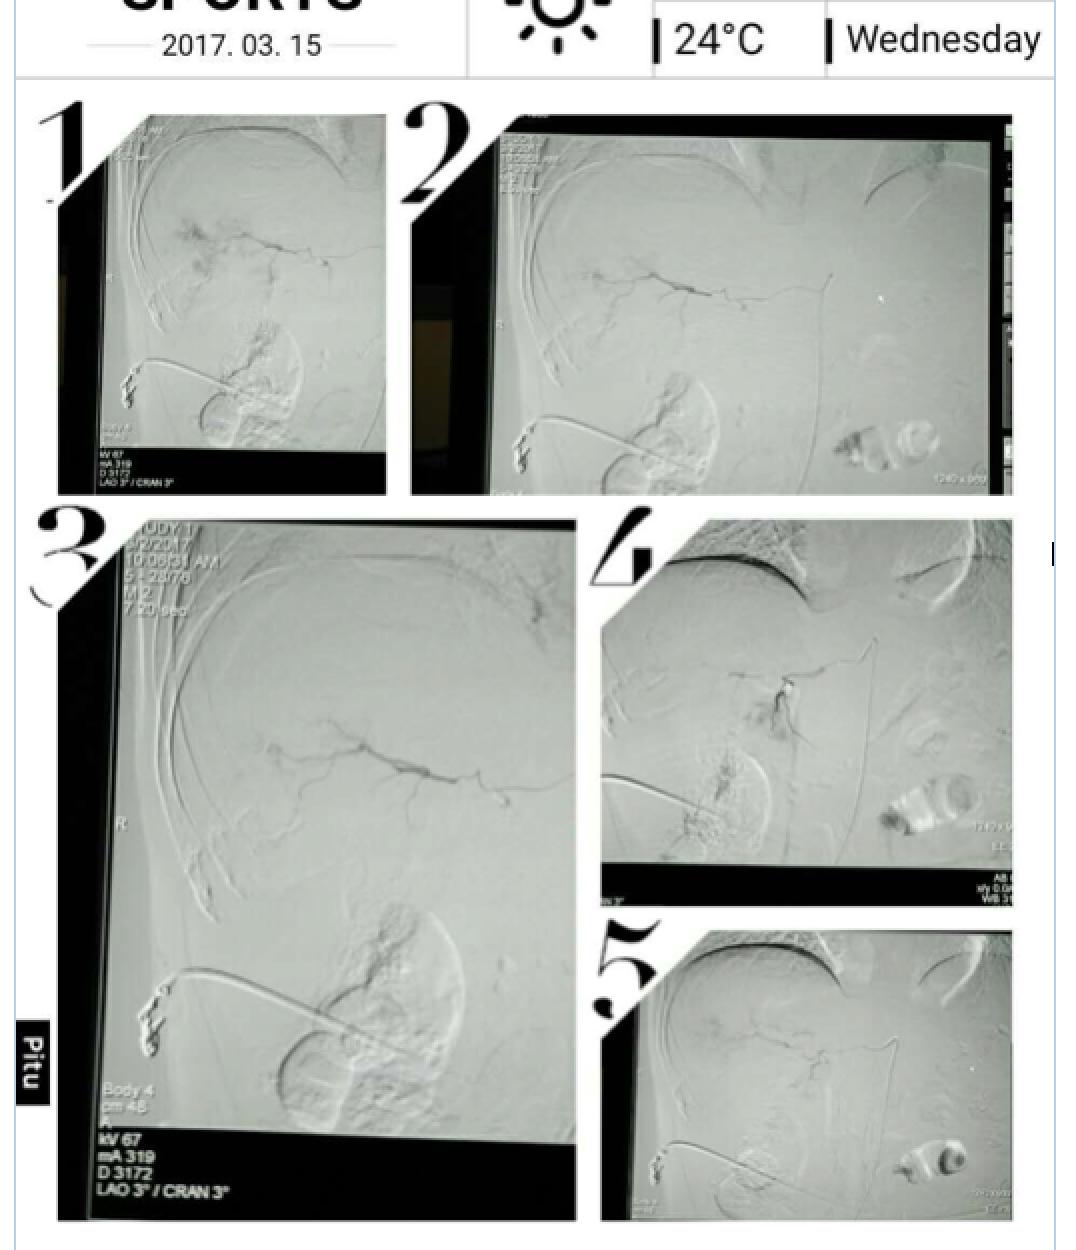

患者因纳差、烧心、腹痛、腹胀2月,于2016-01-17在某县人民医院行腹部CT示肝癌并门脉癌栓形成。分别于2016-01-22、2016-02-19于某市医院行两次TACE术(具体不详)。患者介入术后规律服用抗乙肝病毒、保肝、提高免疫力等药物治疗。2016-02-03至2016-04-30在某省立医院行5周期CIK免疫治疗。2016-05-18至2016-05-25于我院行射波刀治疗门静脉癌栓,具体放疗计划为:42Gy/7F。2016-06-24在我院行肝右动脉化疗栓塞术+肝右动脉灌注化疗术+间接门脉灌注化疗术,术中化疗总量,吡柔比星2mg、顺铂12mg、氟尿嘧啶250mg。分别于2016-05-10、2016-05-27、2016-06-13、2016-07-01、2016-07-27、2016-08-22、2016-09-19、2016-10-07、2016-10-19、2016-11-18、2016-12-18、2017-02-18行12周期免疫治疗。自2016-05-12起患者间断口服靶向药物阿帕替尼250-500mg/d,血压维持在220-130/95-70mmHg,血压升高期间伴上腹部不适,左侧为著,并向腰背部放射,偶尔反酸、烧心,剑突下疼痛,口服抑酸剂或进食后缓解,临床诊断为十二指肠溃疡,目前口服奥美拉唑、马来酸依那普利、氢氯噻嗪等药物对症降压。2017-03-02于我院行第二次肝右动脉化疗栓塞术+肝右动脉灌注化疗术+间接门脉造影术+肠系膜上动脉灌注化疗术。术中化疗总量,洛铂10mg、氟尿嘧啶500mg、吉西他滨400mg。目前间或皮下注射胸腺法新、重组人干扰素α-2b提高免疫力及慢性乙型病毒性肝炎治疗效果。

患者相关影像资料

4. 2017-3-15 DSA造影图中显示肿瘤组织血供一般,也未见癌栓显影,说明肿瘤组织或癌栓血供一般,也可能是靶向药物+栓塞化疗后,主要供血血管已闭塞,继续栓塞治疗效果有限。